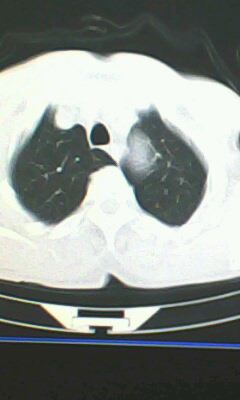

标题: CT26182:男 胸憋 无其它异常症状

胸廓呈桶状,双膈低平,肺实质及纵隔未见明显异常密度灶考虑肺气肿.

胰尾部占位?

未见明显异常。“胰尾占位”为肠管

弥漫性肺气肿 但内胆管轻度扩张